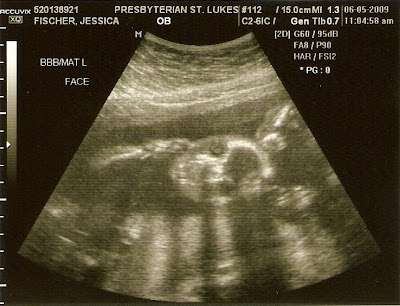

Here is our picture from this week... well, we are in there somewhere, all crunched together! We are growing stronger by the day and we let Mommy know every time that we move! We love it when Mommy eats food and drinks water! It makes us happy and we like tumbling and swimming around, especially when she eats mexican food. We love the spicy stuff already!!